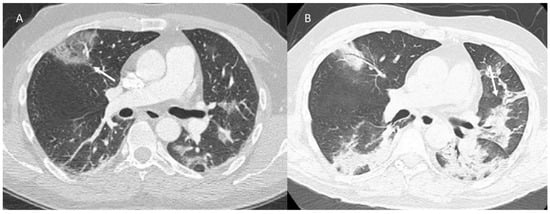

2.1. COVID-19 Vaccine Radiation Recall

| Type of Pneumonia | Lung Involvement | CT-Patter |

|---|---|---|

| COVID-19 Pneumonia | Diffuse (related to the phase of disease) | ground-glass opacity, crazy-paving pattern, consolidative opacities, interlobular septal thickening (according to the phase of disease) |

| RRR-Related Vaccine | Target Area | Consolidative opacities |

| Pulmonary lymphangitis carcinomatosa | Diffuse (related to the phase of disease) | Irregularly interlobular septal thickening, smooth (early stage), or nodular thickening (late development), ground-glass opacity, pleural effusions. |

| ICI-Related Pneumonitis | Diffuse (related to the phase of disease) | ground-glass and reticular opacities, consolidative opacities, interlobular septal thickening, “crazy-paving” pattern |